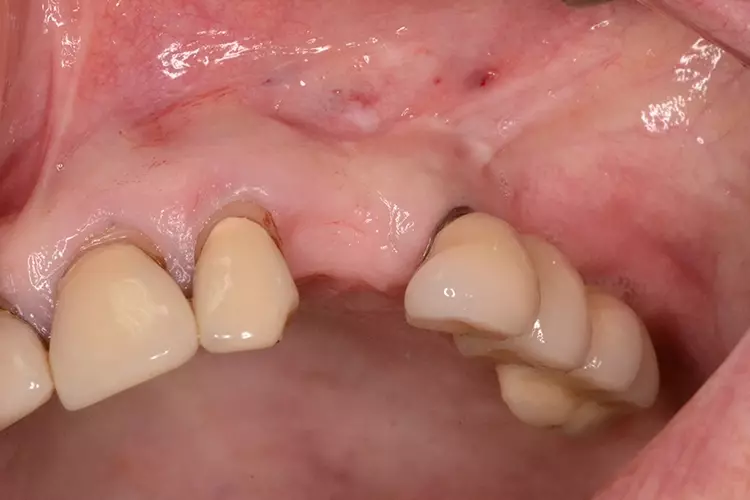

Bei dem heute 49-jährigen Patienten wurde seit Kindertagen versäumt, die Ober- und Unterkieferzahnbögen kieferorthopädisch auszurichten. Der Patient leidet seitdem stark unter seinen Zahnfehlstellungen.

Die Fraktur des stark elongierten Zahnes 21 war für den Patienten der Ausgangspunkt, sowohl die Front des Ober- als auch des Unterkiefers prothetisch überarbeiten zu lassen. Dabei wurde der frakturierte Zahn 21 durch ein navigiert eingesetztes Sofortimplantat ersetzt, während die verschachtelt stehenden Zähne 12 und 42 durch eine Brückenversorgung korrigiert wurden (Abb. 4a-j).